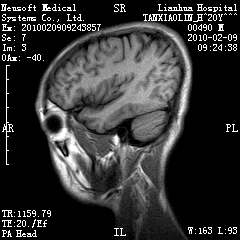

20岁男性患者,平时偶有头痛而无其他不适,现因持续头痛服药后无缓解而来院就诊。

松果体囊肿?

松果体区占位继发轻度脑积水?该患者有ct资料,我已发上。

考虑松果体囊肿。